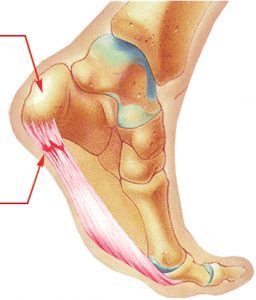

Dolor del talón

Fascitis plantar

Pies

Podología

Podología Deportiva